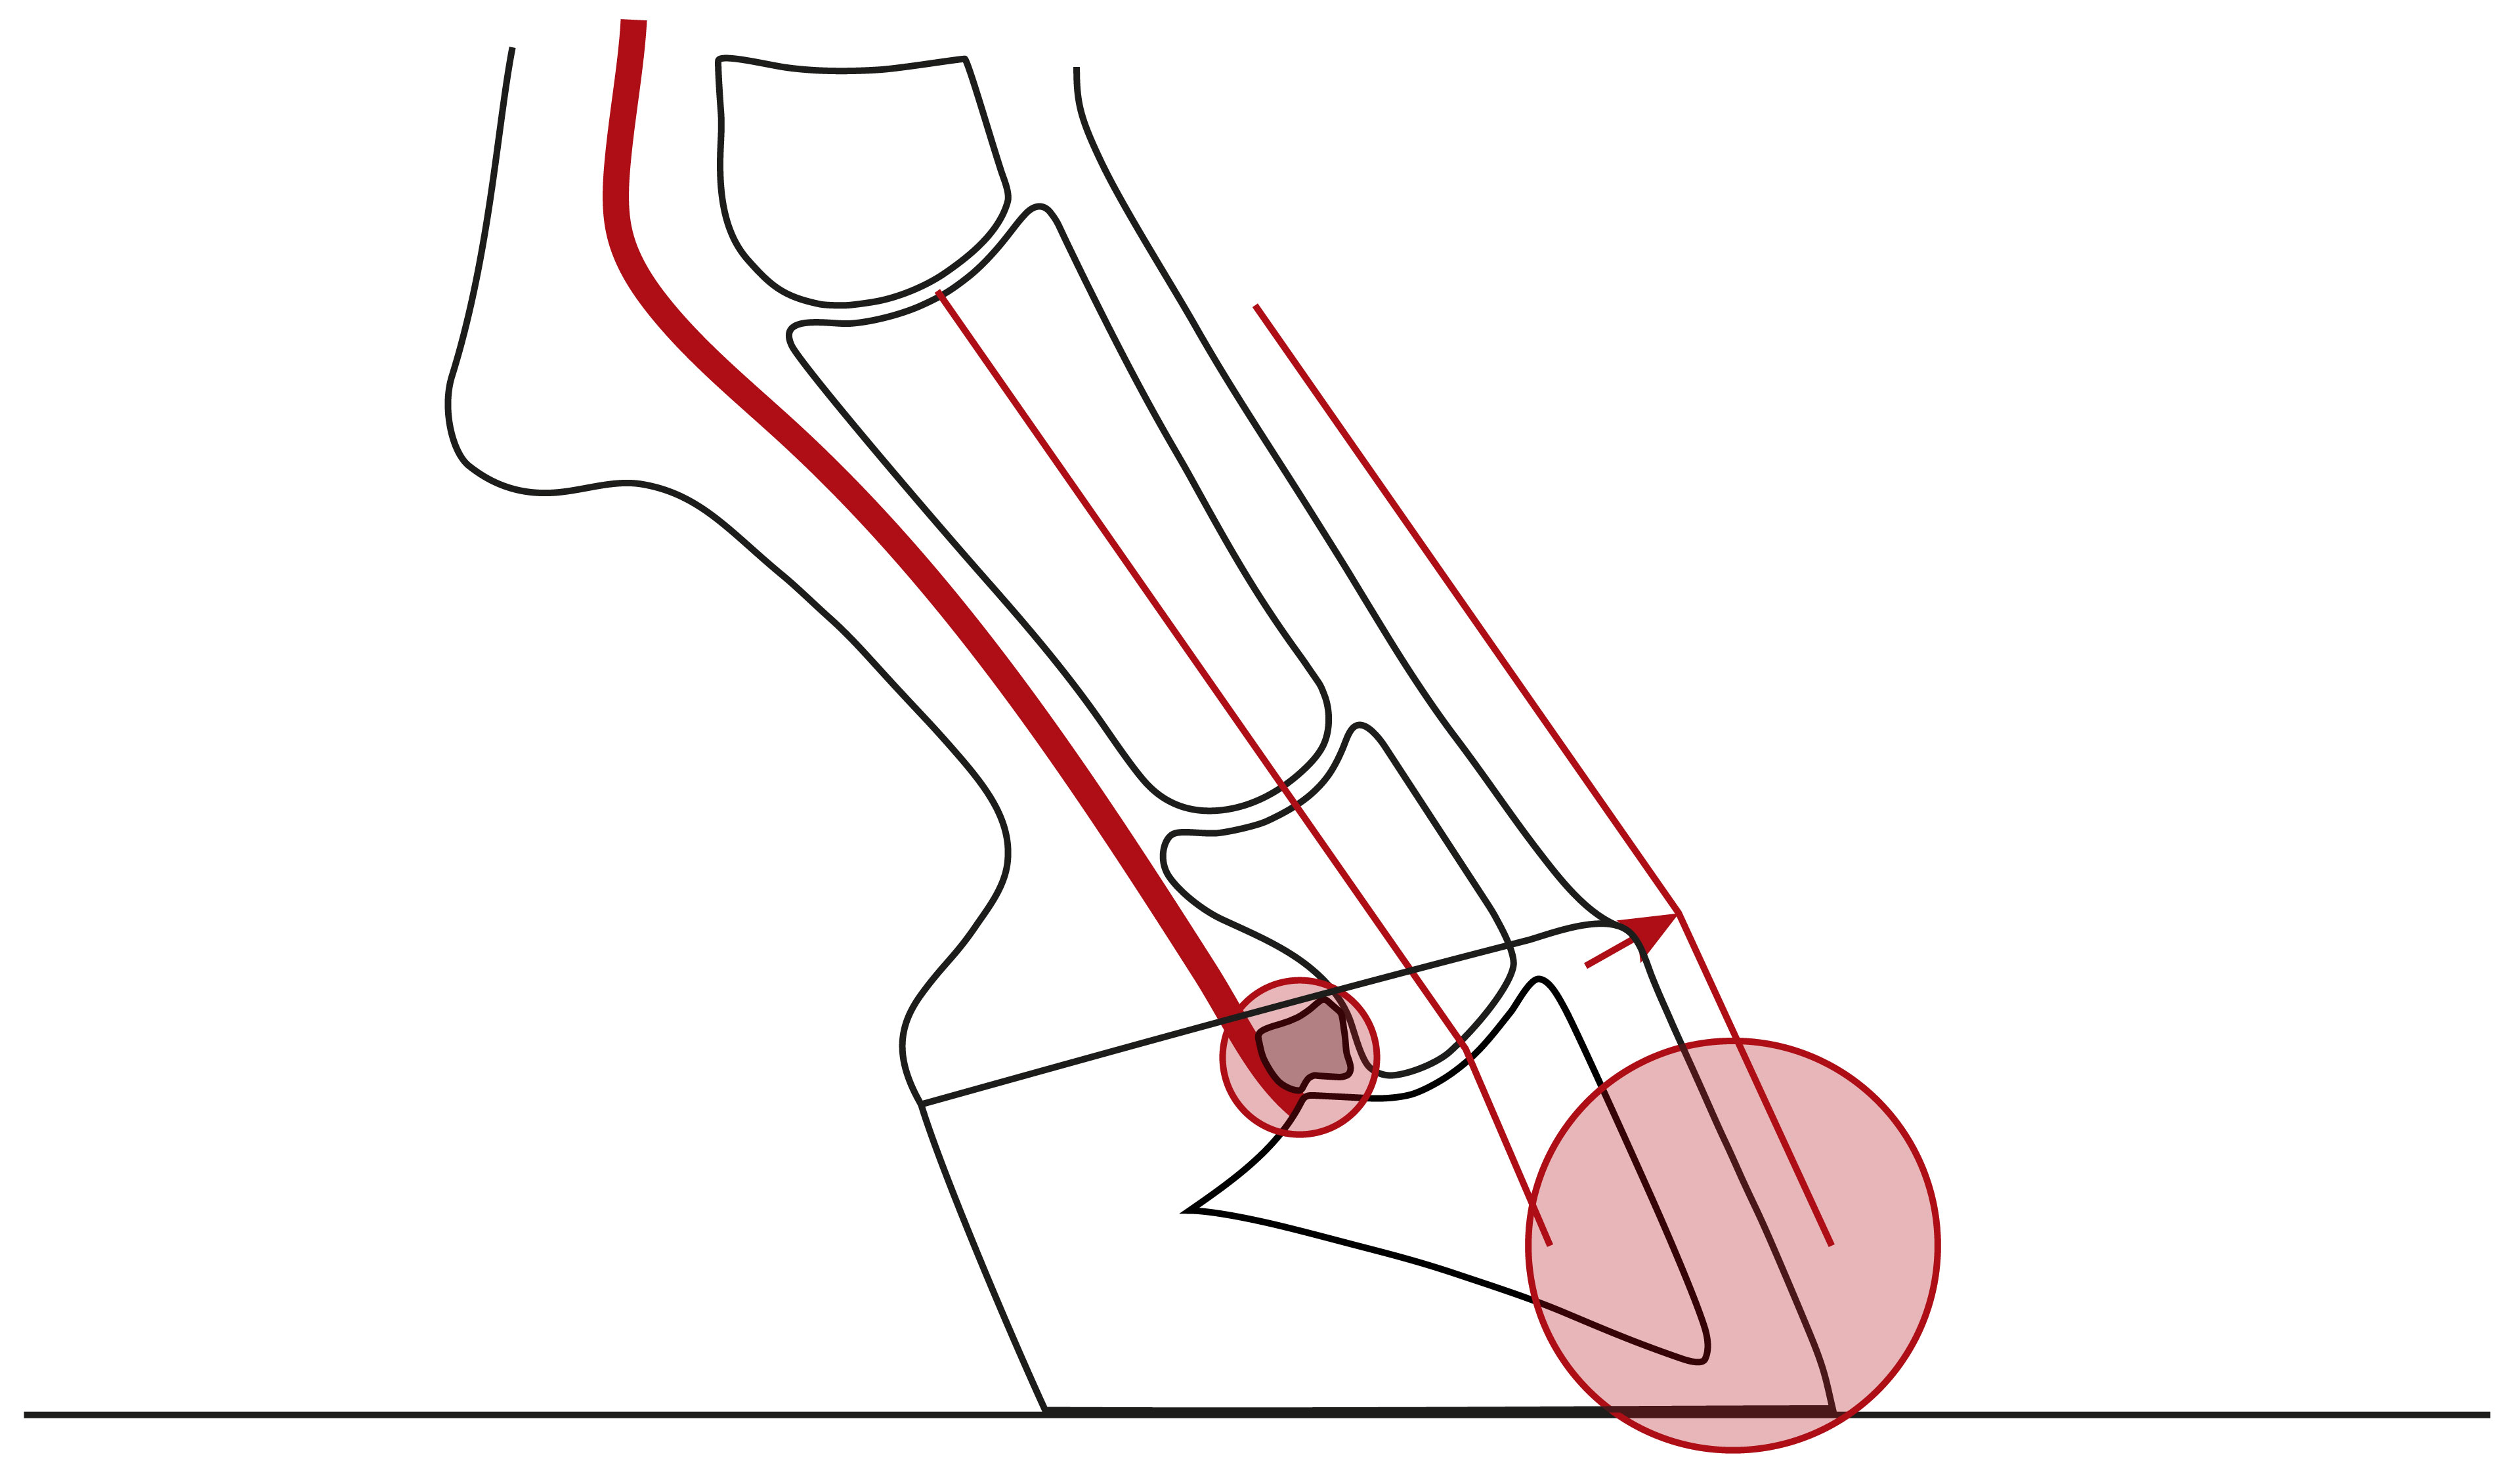

Illustration einer nach hinten gebrochenen Huf-Fessel-Achse mit einer Überstreckung von Huf- und/oder Krongelenk und einer Überlastung der Trachten, des Hufrollenschleimbeutels und ggf. der tiefen Beugesehne

Nach hinten gebrochene Huf-Fessel-Achse mit einer Überstreckung von Huf- und/oder Krongelenk und einer Überlastung der Trachten, des Hufrollenschleimbeutels und ggf. der tiefen Beugesehne.

Illustration einer nach hinten gebrochenen Huf-Fessel-Achse mit einem verbreiterten Hufbeinträger und einer Überlastung der Trachten

Nach hinten gebrochene Huf-Fessel-Achse mit einem verbreiterten Hufbeinträger und einer Überlastung der Trachten.

Illustration einer nach vorne gebrochenen Huf-Fessel-Achse mit einer Beugung des Hufgelenks und einer höheren Belastung der Zehe

Nach vorne gebrochene Huf-Fessel-Achse, stets mit Beugung des Hufgelenks und einer höheren Belastung der Zehe.

Illustration einer nach vorne gebrochenen Huf-Fessel-Achse, verursacht durch die stark angespannte tiefe Beugesehne eines Sehnenstelzfußes

Nach vorne gebrochene Huf-Fessel-Achse, verursacht durch die stark angespannte tiefe Beugesehne eines Sehnenstelzfußes. Zehe, tiefe Beugesehne und Hufrollenschleimbeutel werden dadurch stark belastet.

Illustration mit einer nach vorne gebrochenen Huf-Fessel-Achse und konkavem Verlauf der Zehe aufgrund zu sehr gekürzten Trachten

Werden die Trachten zu sehr gekürzt, führt das zu einer Überlastung der Zehe, der tiefen Beugesehne und des Hufrollenschleimbeutels.